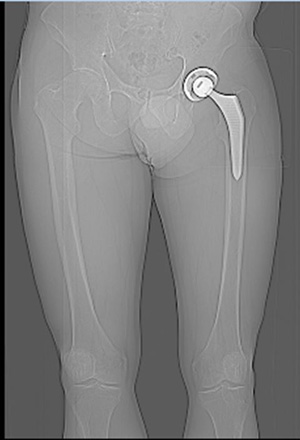

1.2

Wurde ein neues Hüftgelenk eingebaut, wegen den Schmerzen in der Leiste.

1.3

Nun sieht man, dass die Bein- und Gelenk-Stellung nicht übereinstimmt.

Die Schmerzen sind geblieben.